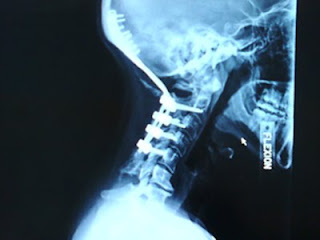

This group of doctors has their own MRI so I was able to get in pretty quickly, and get back in for results a few days after that, which puts us at last week. Let me explain just a little of what you are seeing: you will notice that the spine consists of vertebrae that basically look like little square boxes. Sure, the lines are a wee bit sloppy, but squares all the same. You with me? Now look underneath the hardware. There are two squares there that are WAY out of whack. Both of those squares have one side that is nothing like a straight line. Instead, there's a huge pointy object sticking out of each vertebra. That's not normal, nor is it good. Those points are shoving straight into my esophagus. Directly on the other side of the vertebrae, my spinal cord is being shoved into. That isn't news, but it has definitely gotten worse.

The progression in the spine doesn't surprise me. That my esophagus has pointy pieces of bone pushing it in, yeah that came out of nowhere. The surgeon and the PA explained this is why my voice cracks so much, why it's scratchy and has to be cleared a lot, etc. It makes sense, given I have a spine in my esophagus.